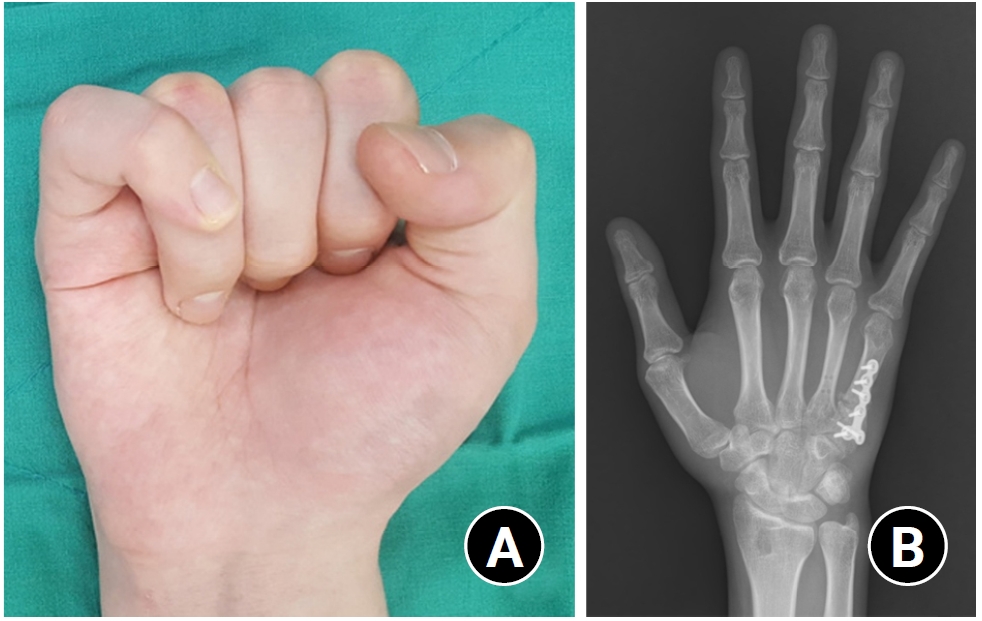

(1) Angular deformity >15° in the middle and proximal phalanges; (2) articular incongruity; (3) angular deformity >10° in the index and middle metacarpal bones; (4) angular deformity >20° in the ring finger metacarpal bone; (5) angular deformity >30° in the little finger metacarpal bone; (6) rotational malunion >10° in the metacarpal bone (Fig. 2).

Rotational malunions can cause finger overlap and are less tolerated as adjacent joints cannot compensate for the deformity [25]. As little as 5° of rotational malunion can cause 1.5cm of finger overlap [2]. Rotational osteotomies can be performed at the fracture site or at the proximal base as described by Weckesser [29], allowing correction of up to 18° for the index, middle, and ring metacarpal bones and up to 30° for the little finger metacarpal bone. In cases with significant angular deformity, the osteotomy at the fracture site is a better surgical technique for simultaneously correcting both rotational and angular deformities [25]. Another excellent option for rotational deformities is the proximal step-cut osteotomy first described by Manktelow et al. [30], which allows for greater bone contact area and fixation with lag screws without the use of bulky plates. Fixation can be performed with K-wires or plates and screws. Many studies have been published on the results with high healing rates, deformity correction, and patient satisfaction of correction of rotational malunions with the above techniques.

Fig. 2.

(A) A case with rotational malunion of the fifth metacarpal bone that induces finger scissoring and disability. (B) Finger scissoring can be corrected by derotational osteotomy.

Fig. 2. (A) A case with rotational malunion of the fifth metacarpal bone that induces finger scissoring and disability. (B) Finger scissoring can be corrected by derotational osteotomy.